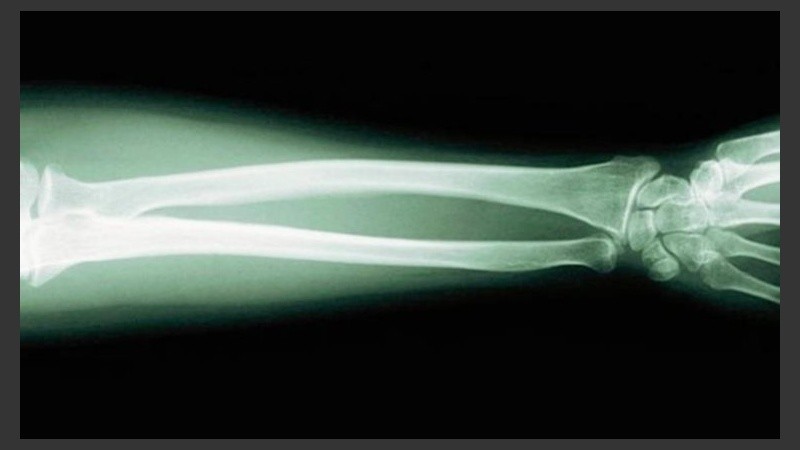

El osteosarcoma es un tipo de cáncer óseo que afecta sobre todo a varones con edades comprendidas entre los 10 y los 30 años. De hecho, elosteosarcoma se corresponde con el cáncer de hueso primario más común en niños y adolescentes. Y si bien la supervivencia a los cinco años es de únicamente un 15-30% en las fases avanzadas –es decir, cuando el tumor ya se ha extendido a otros órganos–, puede ser detenido, según concluye un estudio llevado a cabo por investigadores del Centro Oncológico Princesa Margarita de Toronto (Canadá) y publicado en la revista «Science Translational Medicine».